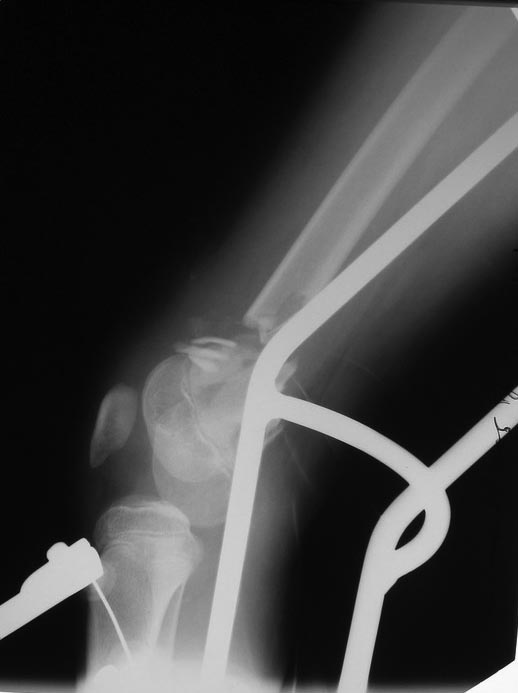

Переломы оскольчатые обеих бёдер в н/3, открытые. Раны ушиты в отличном состоянии.

На одном бедре межмыщелковый перелом и там мыщелки немного разъехались. Голень там тоже сломана в н/3 обе кости. Снимок голени в боковой проекции сделан не был.

Сложный случай. Я бы попробовал бедро с межмыщелковым переломом синтезировать закрыто мыщелки канюлированым шурупом(надеюсь он у Вас есть)и 4-5 спицами антеградно с н/3 диафиза бедра(в идеале под ЕОП контролем).Второе бедро- открыться, стержень Богданова,спицу в дистальный фрагмент через отверстие в стержне,серкляж. Коксит обязательно.Голень тоже нужно репонировать(вальгус слишком большой)и синтезировать спицами антеградно.

Роман не пойму зачем открывать бедро и синтезировать там где второе бедро, да ещё серкляж, это открытый перелом который ушили, а вы туда штифт и проволоку только ради репозиции большого осколка осколка?!. В таких условиях это большой риск остеомилита. Первое бедро где мыщелки смещены открыто стоит риска так как там большая вероятность контрактуры. Вытяжение при ограниченных ресурсах следует продолжить. Где второе бедро нужно наложить боковое манжеточное вытяжение предварительно отрепонировав его насколько возможно. Первое бедро попробовать отрепонировать или идти открыто с учётом характера раны и возможного доступа. Фиксация толстыми короткими спицами. На голень лонгету и спицы. Тамже можно Лфк с лонгетой на ноге.

Голень отрепонировать закрыто и фиксировать спицами + гипс ниже колена. На оба бедра, если нет возможности адекватной внутренней фиксации - аппарат.

Глубокоуважаемый Игорь. Есть ли в вашем отделении ЭОП? Переломы бёдер не простые. Я бы не стал рассчитывать на скелетное вытяжение. Не очень понятно где какое бедро. Левые снимки – по моему мнению бедро надо оперировать с артротомией: необходимо убрать осколки по передней поверхности перелома – они гарантировано будут мешать движениям. Малоинвазивное удаление может быть неудачным. Синтез мыщелков имеющимися у Вас спицами под контролем глаза и пальца. Кстати, в суставе могут быть обнаружены различные неожиданности. Общую фиксацию можно осуществить в АНФ Илизарова с встречной компрессией мыщелков. Правые снимки. Тоже высокоэнергетический перелом и критическое смещение отломков. Так оставлять, ИМХО, не стоит. Велика вероятность массивной интерпозиции между отломками. Отломки ротированы и это может вызвать нарушение сращения,ремоделирования кости. В качестве варианта: наложение АНФ Илизарова, разрез, «ручная» репозиция отломков «по месту». Дистальные перекрещивающиеся спицы я бы провёл через мыщелки бедра. АНФ будут оптимальны в спице-стержневом исполнении. С уважением!